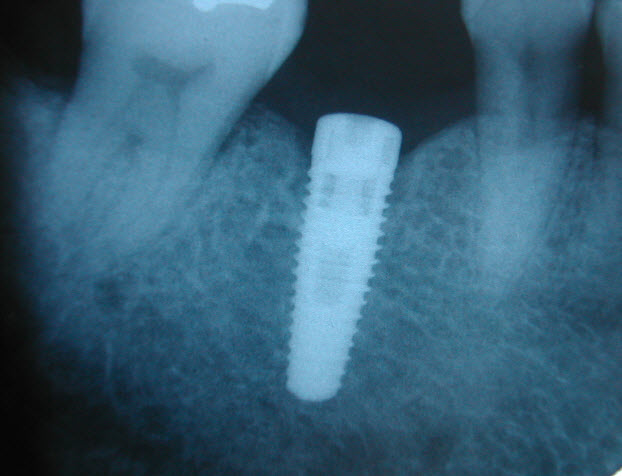

Single Tooth Implant Cost    Hi there,   I got my tooth extracted a while back and now I am ready to have it replaced. How much is the average cost of a single tooth implant?   Can ...AnswerThe cost of a single tooth implant is approximately $3500-$4000.   You would need to have a consultation with the dentist to see if there bone to support an implant and if an implant is the best ...